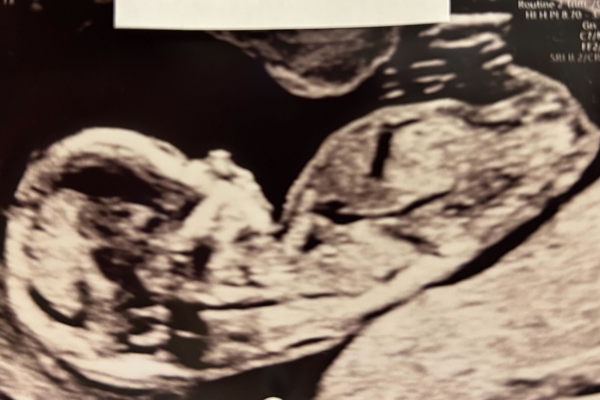

På ultralyd kan man se, hvordan hænderne søger op mod munden, og hvordan arme og ben bøjes og strækkes. Små drenge danner mandligt kønshormon, og hos pigerne er der millioner af primitive anlæg til æg i de umodne æggestokke. Nu kan man også ane de linjer på fingerspidserne, der senere bliver til barnets unikke fingeraftryk. Man kan så småt skelne imellem drenge og piger på scanning. Fra næste uge vil en kønsscanning være meget præcis.